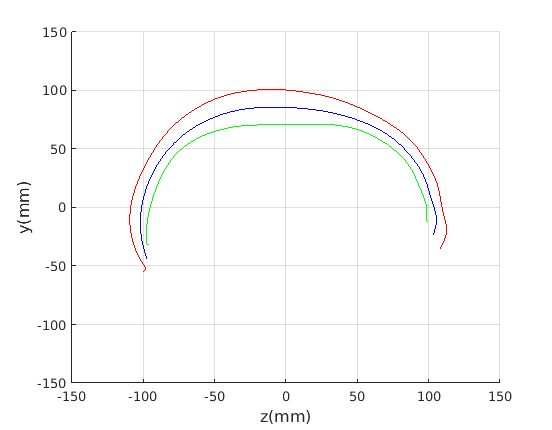

8 A case study of cranial profile model use for intervention outcome evaluation

In this section we take a sample of 25 boys, who are craniofacial craniosynostosis patients, 14 of which have undergone one type of corrective procedure (BS) and the other 11, another corrective procedure (TCR). Providing that the heads are sufficiently symmetrical and are amenable to ellipse fitting, we can parameterise all of these patients’ heads using our scale-normalised craniofacial profile model (2D model with face cropped out). We can then plot their pre-operative and post-operative parametrisations and compare them with the parameterisations of the 100 training examples. The expected result is that the parameterisations should show the head shapes moving nearer to the mean of the training examples. It also reveals which of the dominant modes of shape variation are most affected. The results are shown in figures 31 and 32.

For the BS patient set, the Mahalanobis distance of the mean pre-op parameters (red triangle in Fig. 31) is 4.670, and for the mean post-op parameters (blue triangle) is 2.302. For shape parameter 2 only these figures are 4.400 and 2.156.

For the TCR patient set, the Mahalanobis distance of the mean pre-op parameters (red triangle in Fig. 32) is 4.647, and for the mean post-op parameters (blue triangle) is 2.439. For shape parameter 2 only these figures are 4.354 and 2.439. We note that most of this change occurs in parameter 2, which corresponds to moving height in the cranium from the frontal part of the profile to the rear. In these figures we excluded one patient, who preoperatively already had a near-mean head shape (see red cross near to the origin in Fig. 32, so any operation is unlikely to improve on this (but intervention is required in order to relieve potentially damaging inter-cranial pressure).

It is not possible to make definitive statements relating to one method of intervention compared to another with these relatively small numbers of patients. However, the cranial profile model does show that both procedures on average, lead to a movement of head shape towards the mean of the training population. An example of analysis of intervention outcome for a BS patient is given in Fig. 33 and a TCR patient is given in Fig. 34. The particular example used is highlighted with circles on figures 31 and 32 to indicate pre-op and post-op parametrisations. To our knowledge this is the first use of statistical 3D craniofacial shape models in a clinical study.